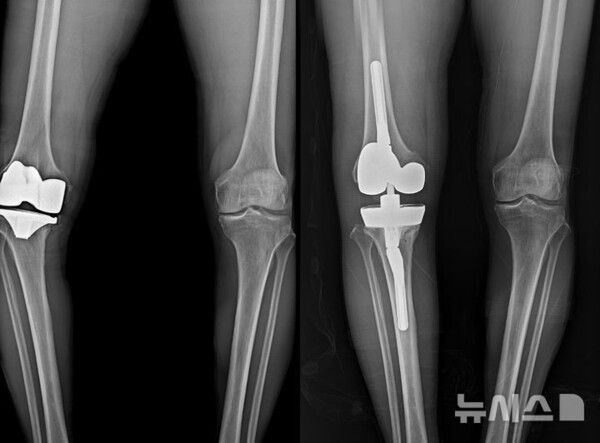

사진 = 뉴시스

보건복지부 지정 관절전문 연세사랑병원은 최근 무릎 인공관절 재치환술 1000례를 달성했다고 25일 밝혔다.

뉴시스 보도에 따르면, 연세사랑병원은 최근 10년 동안에만 833례의 인공관절 재치환술을 시행했다. 무릎 인공관절의 내구성은 현재 평균 20년 정도로 보고되며 과거 10~15년 수준이던 수명이 꾸준히 향상돼 왔다. 이러한 변화는 제3세대 인공관절 디자인의 발전, 네비게이션 수술, 로봇 수술, AI(인공지능) 기반 3D 시뮬레이션, 맞춤형 수술도구 등 다양한 기술이 도입되면서 수술 정확도가 높아진 데에서 비롯된다.

그러나 평균 수명 증가에 따르는 인공 관절 마모뿐 아니라 부정정렬, 인공관절 불안정성, 해리, 감염 등으로 인해 재수술이 필요한 경우는 여전히 존재하며 국내외 연구에 따르면 전체 인공관절 수술의 약 5~10%가 재치환이 필요한 것으로 알려져 있다.

문제는 재수술이 첫 수술보다 훨씬 복잡하고 고난도의 기술을 요구한다는 점이다. 연세사랑병원의 자체 집계에 따르면 지난 10년간 무릎 인공관절 재수술을 받은 환자 833명 중 58%인 483명이 70대 이상의 고령이었다. 고령 환자의 경우 동반된 기저질환을 고려해야 하기 때문에 수술 전 환자 평가를 위한 내과 전문의와의 협진이 필수적이다.

또 재수술 원인 분석을 위한 영상의학적 진단, 감염·통증 관리 등을 위한 마취통증의학과 협업, 수술 후 재활 프로그램 등 다학제 시스템이 필요하다. 이러한 체계를 충분히 갖춘 병원이 많지 않기 때문에 재수술이 필요한 환자 중 상당수는 첫 수술 당시와 비슷하거나 더 심한 통증으로 생활에 어려움을 겪는 경우도 적지 않은 것으로 알려져 있다.

연세사랑병원 인공관절재수술센터는 1000례에 달하는 풍부한 재수술 경험을 기반으로 수술의 안정성과 효율성을 높이고 있다. 병원은 앞서 설명한 재수술의 까다로움과 어려움을 줄이기 위해 정형외과, 내과, 영상의학과, 통증의학과의 협진 시스템을 구축했다. 이를 통해 ▲정확한 원인 진단 ▲증상과 상태에 맞는 수술 및 치료 ▲수술 후 통증 관리 ▲재활까지 환자 개개인에 맞는 치료를 진행한다.

의료진의 임상경험과 잘 구축된 시스템을 바탕으로 수술시간도 줄어들었다. 일반적으로 재수술은 첫 수술에 비해 두 배 이상의 시간이 소요되는 것으로 알려져 있다. 그러나 연세사랑병원 재수술센터의 평균 수술 시간은 1시간 10~20분 가량으로 첫 수술 평균 40~50분의 소요시간에 비해 30분 정도만 더 소요된다.